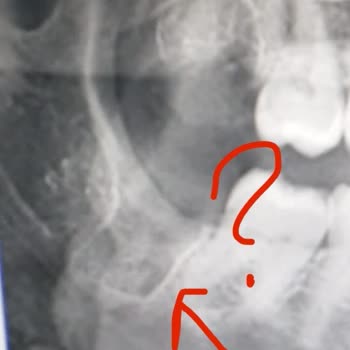

Ben 24.10.2024 Sakadent'te 20'lik dişimi çektirdim eksik tedavi uygulamasından ötürü tekrar başka bir özele gitmek zorunda kaldım. Çünkü 20lik dişin apse yapmış olmasına rağmen dikiş atılmadı İlk tedavide dikiş atılması gerekirken bir şey yapılmadığını şikayet etmek istiyorum. Hatta ve hatta çekilen...